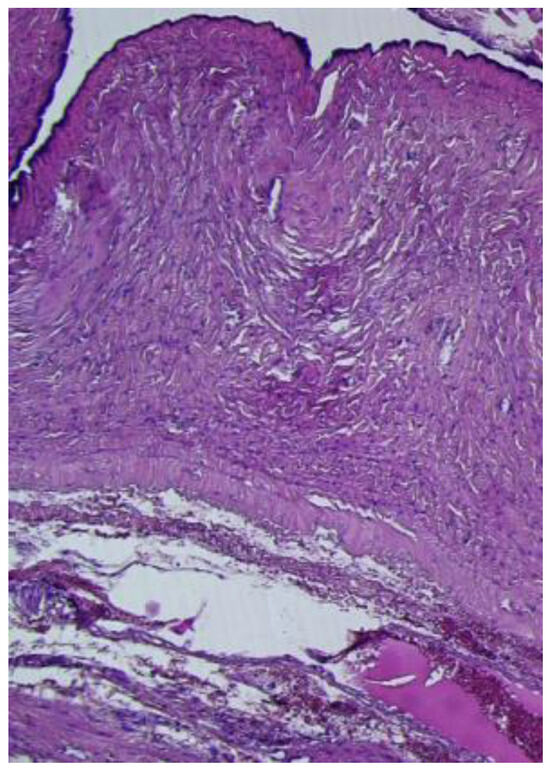

The histopathological microscopic assessment of the first structure revealed a cyst wall lined by a ciliated tubal-type epithelium (Figure 5), with endosalpingeal focal papillary projections.

Figure 5. Paratubal cyst lined by pseudostratified and simple columnar epithelium (HE ×20).